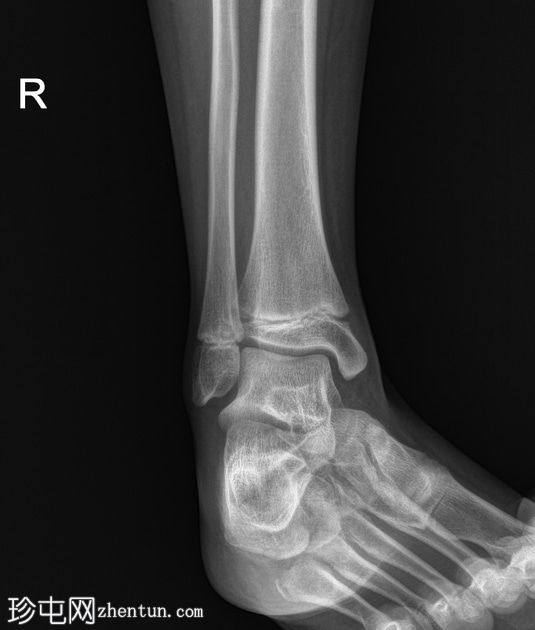

X线片

斜位片

双侧跟骨密度增高,可见跟骨骨骺碎片,提示跟骨骨骺炎,又称塞弗氏病。

塞弗氏病,又称跟骨骨骺炎,是生长发育期儿童足跟(或跟骨)生长板后方的炎症。

该病被认为是由足跟反复受力引起的。这种疾病良性且常见,通常在生长板闭合后或活动量减少时缓解。